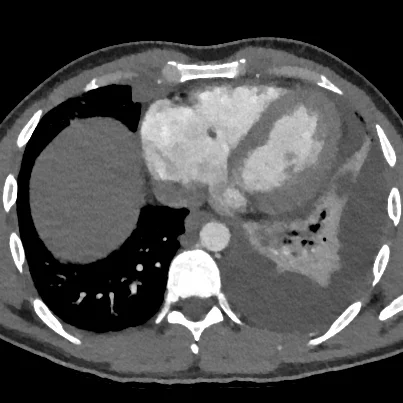

Large embolus in right lower lobe

Note subtle vegetation adjacent to the tricuspid valve